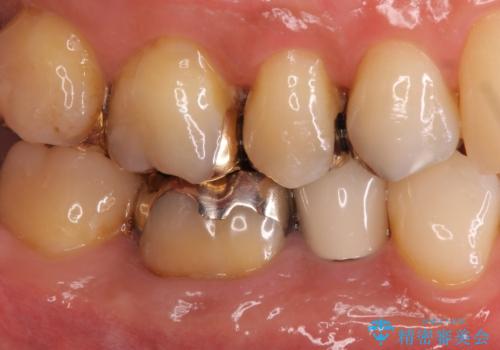

目立つ銀歯を白くしたい ジルコニアクラウンでの修復

- 口を開けたときに下の歯の銀歯が目立つから白くしたいとのことで来院されました。

根管治療はご希望されなかったため、被せ物のみをやり替えていきます。

- 右下6 仮歯+ジルコニアクラウン 11,000円+121,000円費用は治療当時の料金となります